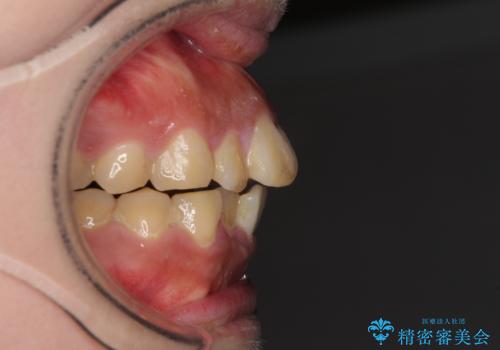

- 口元の突出感と上下前歯のでこぼこを気にして来院された患者様です。

上下前歯部叢生のスペース獲得のため、上下顎左右小臼歯各1歯(計4本)を抜歯して、矯正治療を行うこととしました。